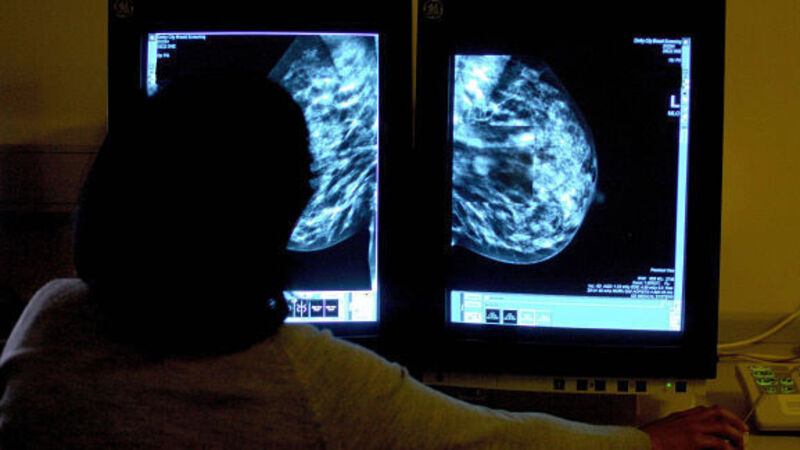

More women with breast cancer could be spared chemotherapy if doctors switched to a new genetic test, research shows.

The EndoPredict test can more accurately predict whether a woman's cancer will spread around the body.